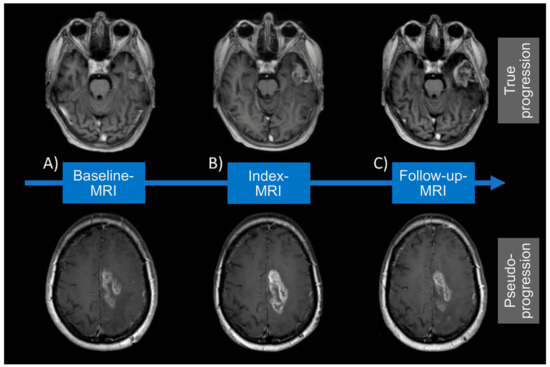

2.4. Definition of MRI Acquisition Time Points

2.5. Diagnosis of True Progression/Pseudoprogression